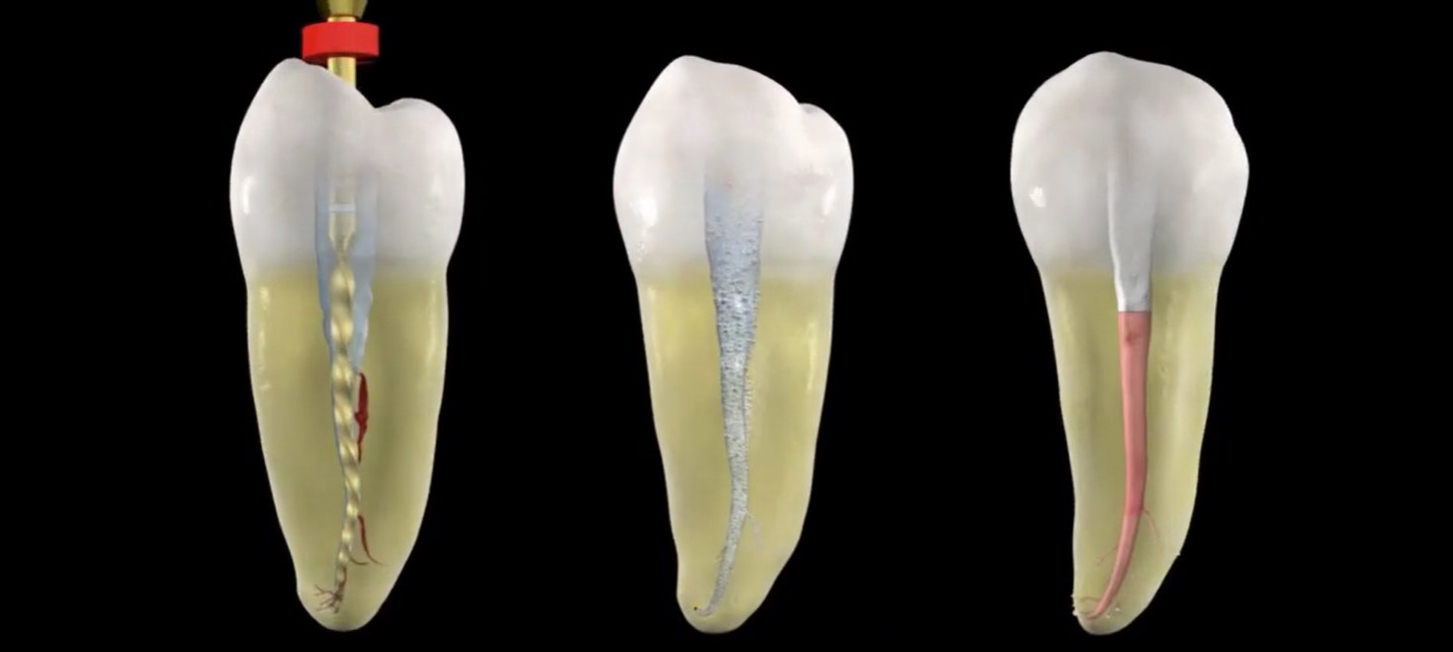

Endodontic Canal Preparation: Reciprocation

Endodontic Canal Preparation: Rotary